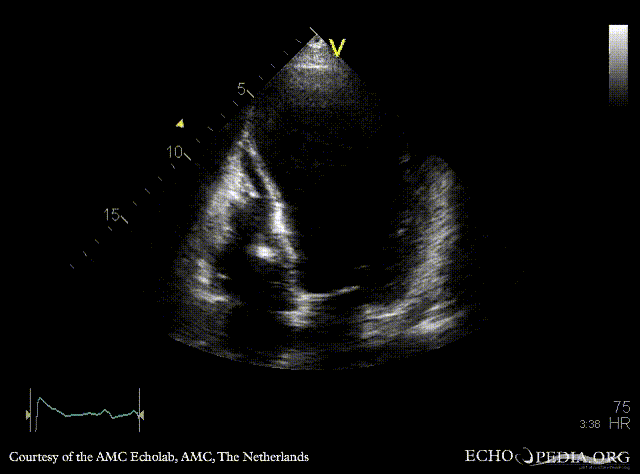

Large aneurysm of LV

A4CH: large apical aneurysm of left ventricle, spontaneous echocontrast